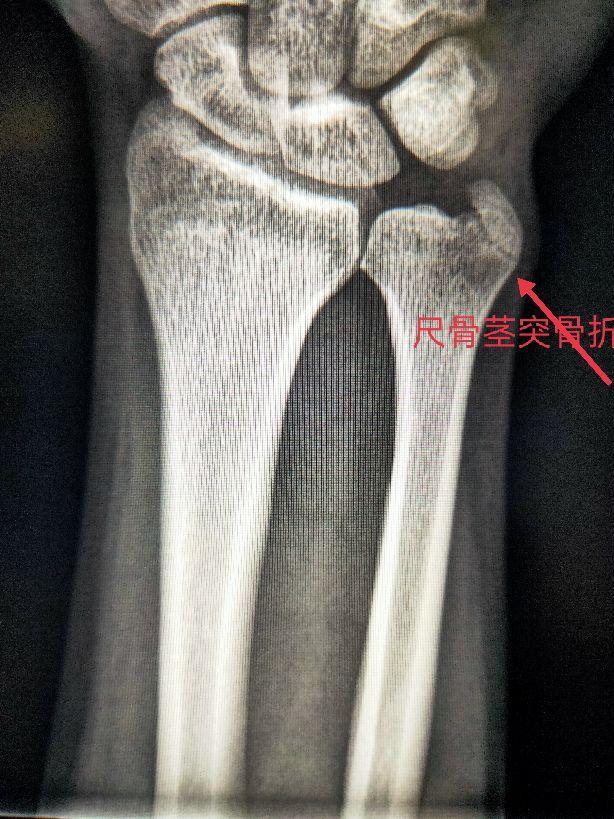

四、尺、桡骨骨折X线片

尺骨桡骨骨折以桡骨远端骨折多见。其次是尺骨桡骨双骨折,多发生于青少年。